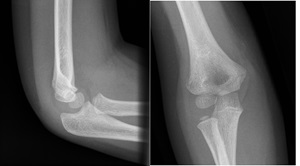

Example X-rays

|

Anterior fat pad seen but NOT elevated, so NOT a joint effusion |

Anterior fat pad elevated off anterior surface of humerus = joint effusion |

A posterior fat pad is always abnormal |